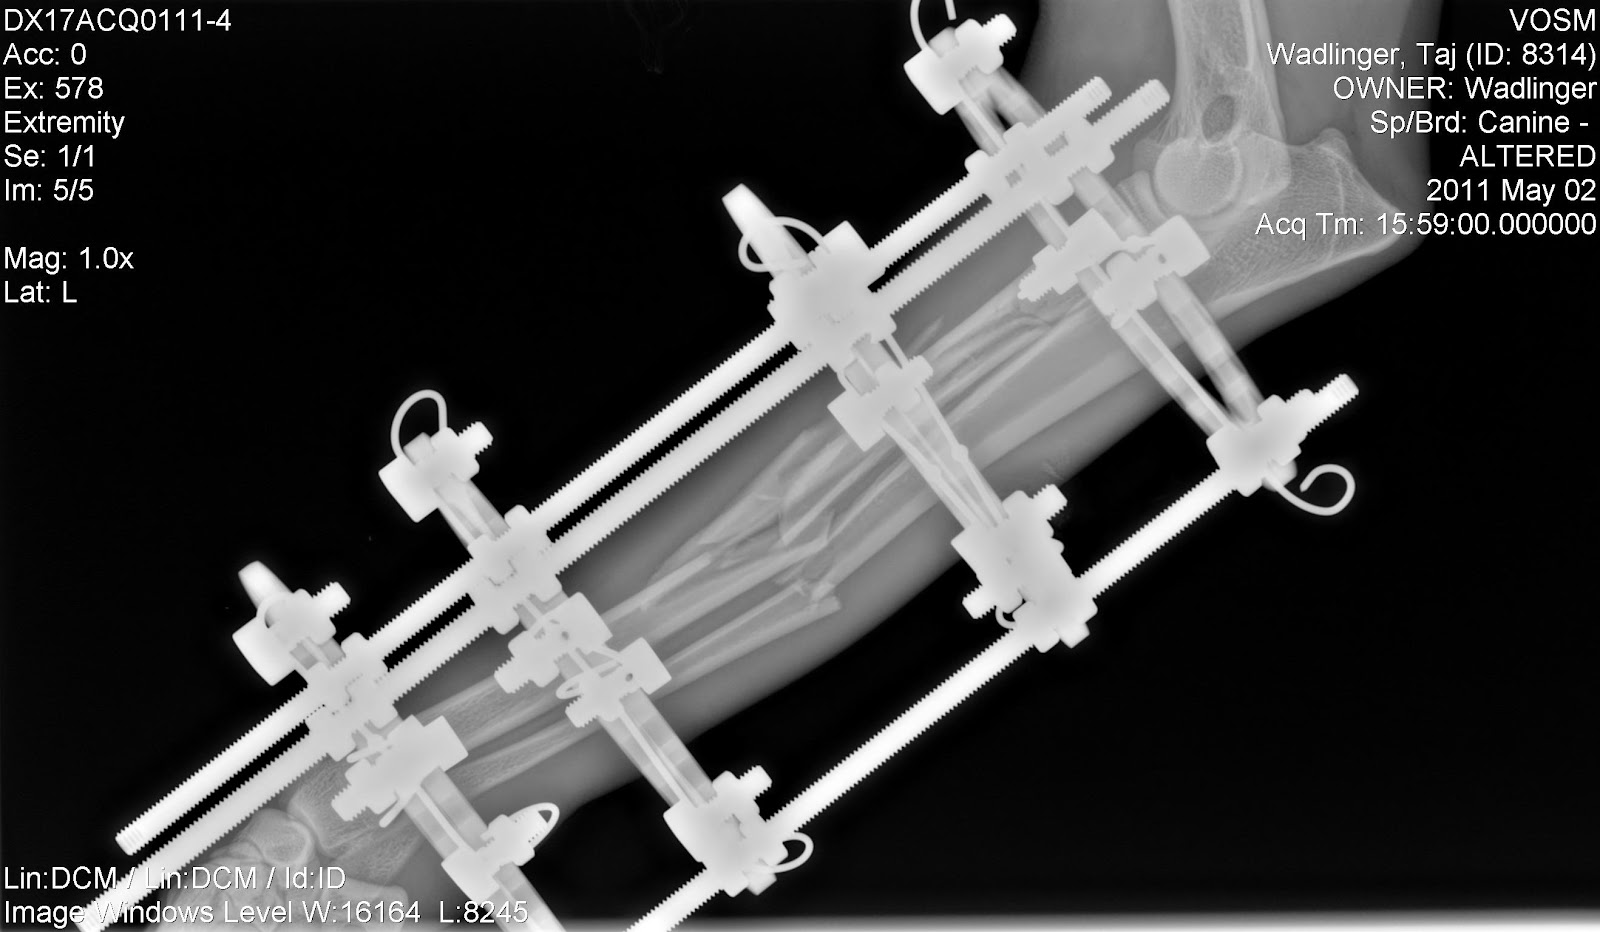

Post-surgery:

Post-operative radiographs confirmed appropriate implant positioning and good anatomic alignment (elbow over wrist). Perfect reduction was not attempted due to the severe comminuted nature of the fracture. Perfect positioning of the bone fragments is not necessary, and clinical studies have shown that disturbing a break with internal surgery can sometimes: slow the healing process by disturbing the fracture hematoma and periosteal blood supply, cause longer surgery times, heighten risk for infection and blood loss, cause higher levels of post-op pain, and possibly more post-surgical complications (Dudley et al.,

J Am Vet Med Assoc., 1997; Johnson et al,

J Am Vet Med Assoc., 1998; Ozsoy & Altunatmaz,

Vet Med Czech, 2003; Schmal et al.,

J Orthop Trauma, 2011).

| Lateral View: Post Fixator Surgery |

Front to Back View:

Post Fixator Surgery |